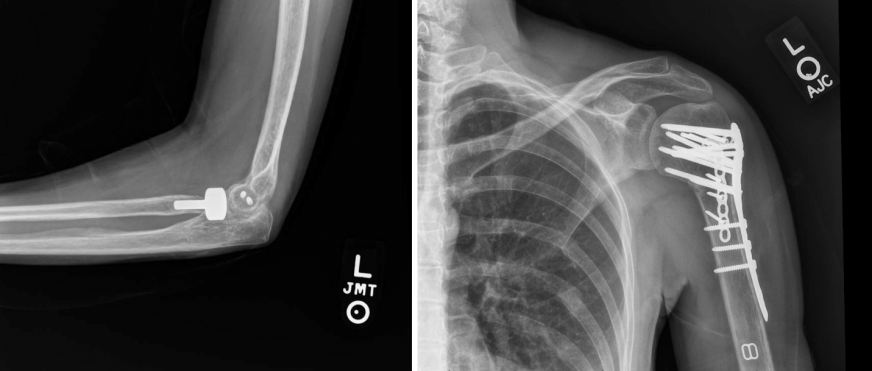

All three injuries were treated during a single procedure. Open reduction and internal fixation (ORIF) was performed on the left shoulder and elbow first, followed by ORIF of the wrist (Fig. 2).

Figure 2: Post-operative lateral left elbow (left) and anteroposterior left shoulder (right) X-rays.

A modified volar Henry approach to the distal radius was utilized in which the incision was made between the radial artery and the flexor carpi radialis tendon. The high-energy nature of the multilevel injury to the left upper extremity resulted in a highly unstable distal radius fracture pattern with a significant amount of metaphyseal radial column comminution. The decision was made to proceed with fragment-specific fixation, and a radial column plate was placed underneath the first extensor compartment in addition to a volar locking plate (Fig. 3).